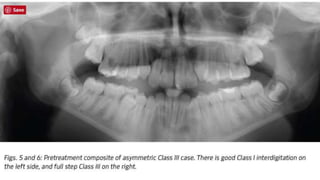

Clinical case A 13-year-oldmale presented for treatment with slight overbite and overjet, and maxillary canines actively erupting toward the buccal . The posterior occlusion was Class I molar left and full step Class III molar on the right side , resulting in a significant mandibular midline discrepancy.

• 71.

The patient hada straight facial profile, good lip competency and mild chin deviation to the left. In spite of the asymmetric Class III dentition, the resulting chin deviation was mild enough to be considered within normal limits

• 72.

Mandibular mid lineis deviated to the left